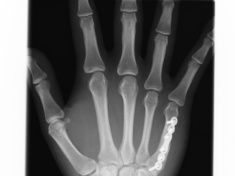

Röntgenbilder